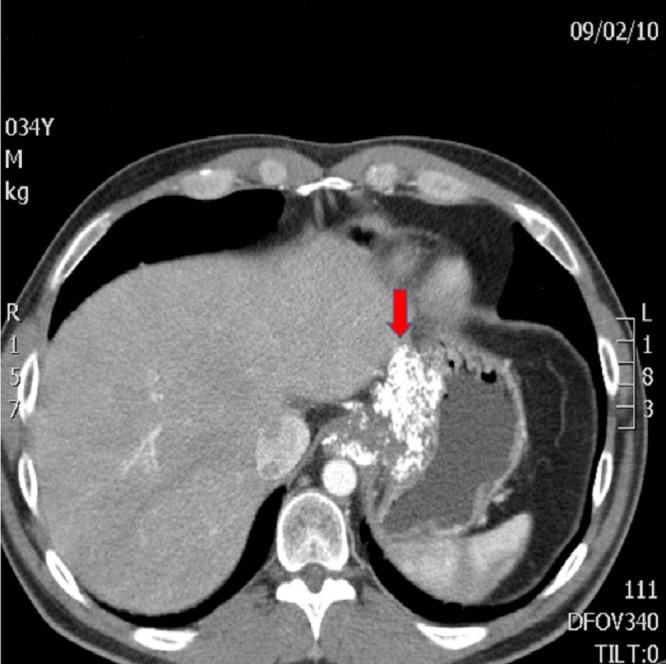

Disease assessment based on measurements of size and anatomic involvement have historically been central to surgical strategy. We propose this to be an outdated concept, which should be replaced by a deeper understanding of tumor biology and careful treatment planning. Report of case: A 34-year-old male was diagnosed with a Siewert Type 3 locally advanced cancer of the gastroesophageal junction, involving the coeliac axis and the superior mesenteric artery (SMA). He was treated with neoadjuvant chemotherapy, followed by chemoradiation, and then proceeded to surgery, at which time the tumor was judged unresectable. After extensive planning, a further surgery was attempted - an extended gastrectomy with distal esophagectomy, left hepatectomy, and splenectomy were performed. Additionally, the coeliac axis and the SMA were excised, followed by reconstruction of the hepatic artery and the SMA with grafts. Adjuvant chemotherapy was administered, and the patient is recurrence-free after five years follow-up.